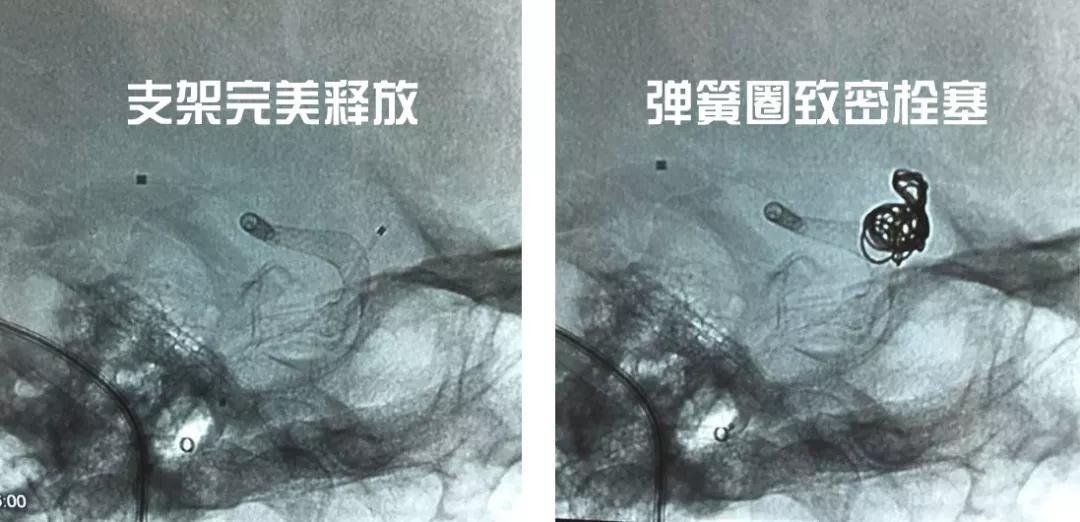

Pipeline密网支架作为血流导向装置的代表,以载瘤动脉重建为理念,通过降低入瘤血流的流速、流量,加速动脉瘤内血栓形成及瘤颈处内皮化,从而达到治疗的目的,对大型或巨大型颅内动脉瘤的治疗结果产生了革命性的变化。文献报告Pipeline治疗颅内大型、巨大型动脉瘤的随访结果提示治愈率92%~100%。由于动脉瘤内不必再填塞弹簧圈(或仅需少量弹簧圈),动脉瘤的占位效应也得到缓解甚至完全解除,同时总体费用低,效果好,是今后颅内大型、巨大型动脉瘤治疗的方向。

与患者家属沟通后,家属同意选择此类动脉瘤介入治疗的最佳方案:Pipeline密网支架加弹簧圈栓塞。在进行了充分的术前准备后,神经外科王增武团队于8月22日行介入手术治疗。术中采用“双导引管、瘤内成袢、推拉释放”等一系列高难技术,稳步攻克各个难关,顺利完成手术。